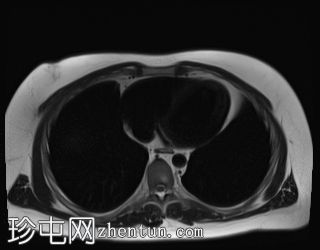

轴位

T2加权像

T1低信号,T2低信号为主的脾脏肿块,内部可见T2高信号分隔,呈进行性强化。肿块中央可见星状瘢痕。

脾脏硬化性血管瘤样结节性转化(SANT),9.8 cm肿块

顾名思义,脾脏硬化性血管瘤样结节性转化(SANT)是一种纤维性血管病变。本病例展示了SANT的一些典型影像学特征,包括边界清晰的病灶,中央可见瘢痕,以及呈放射状进行性强化。这些特征使得术前MRI诊断较为明确。尽管SANT是一种良性病变,但大多数患者仍需行脾切除术以明确病理诊断。